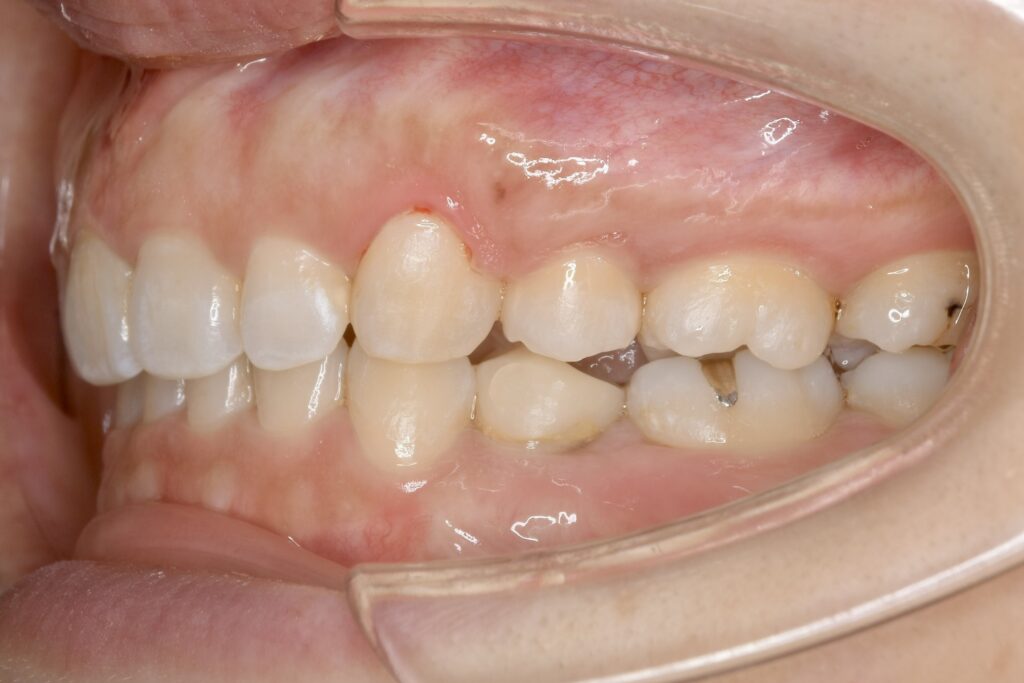

32歳 女性 治療期間:1年7ヶ月

AFTER

診断名・主な症状 叢生を伴う上顎前突

治療内容 上下とも歯を2本抜いて、上の前歯を後方に引きながら、でこぼこを治しました。

使用装置 マウスピース矯正装置(インビザライン)

治療期間 1年7ヶ月

通院回数 13回

費用 91万円程度(税別)   270